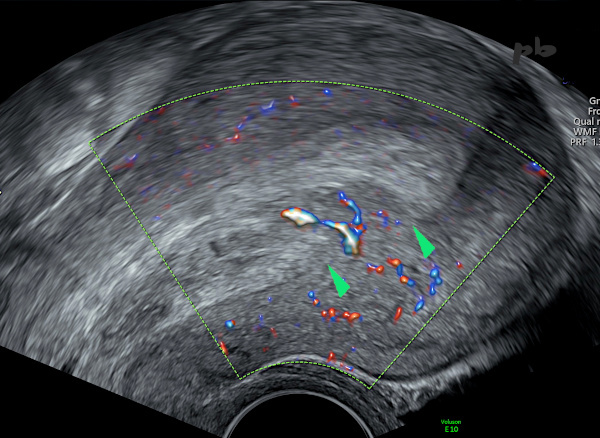

5 – Résidus trophoblastiques

(même patiente que 4)

Echographie doppler – Coupe sagittale.

Muqueuse et cavité utérine très épaissies et hétérogènes.

Entre les 2 marqueurs (►), l’interface endomètre – myomètre disparait : la portion isoéchogène au myomètre est vascularisée, correspondant à des résidus trophoblastiques et non hématiques.